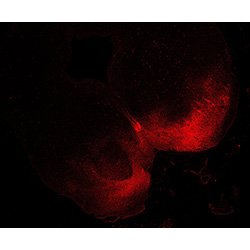

An anatomical analysis of the developing human midbrain from 6 post-conceptional weeks (PCW) to 22 PCW reveals increased tissue complexity, characterized by the emergence of dopaminergic nuclei, as highlighted by immunofluorescence analysis for tyrosine hydroxylase (TH).

22PCW

DAPI

22PCW human midbrain

GFAP

TH

Merged

MAP2